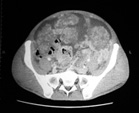

229SPS-07CT01.jpg

CT所見: 大量腹水と腹膜の凹凸不整があり腹膜播種癌性腹膜炎に矛盾しない。直腸壁の不整肥厚は原発性直腸癌の所見であってよい。この他, 両肺野には多数の小結節が認められ肺転移と考えられた。左頸部, 縦隔, 腎門部にはリンパ節腫大を認めた。